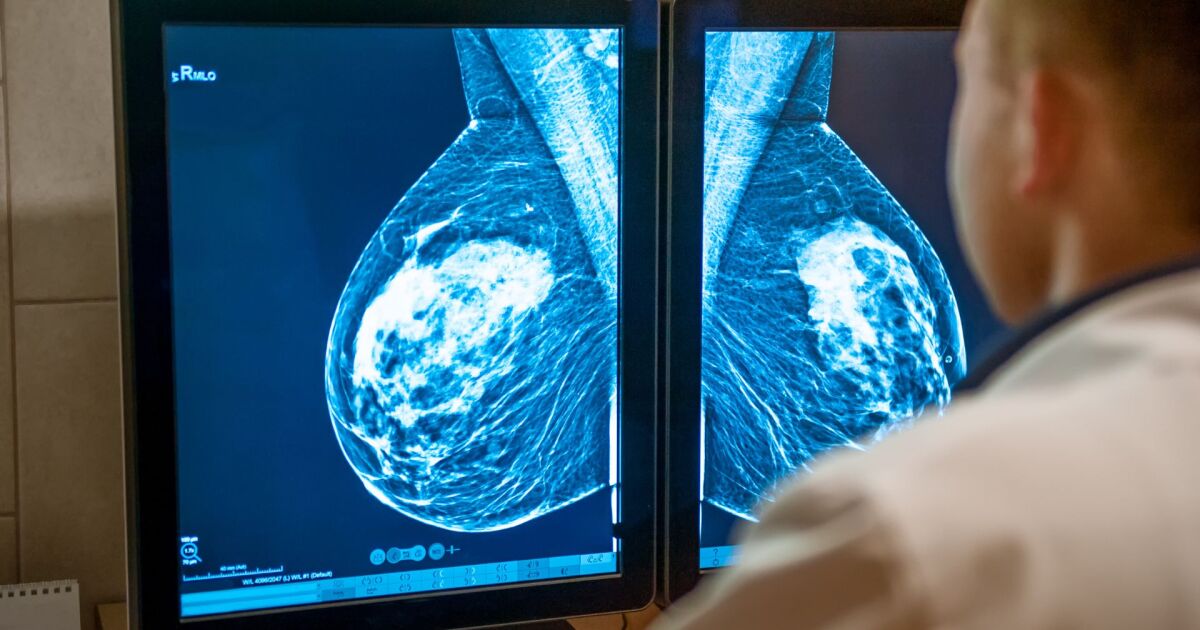

Диагностиката на кистите на гърдата обикновено включва няколко метода, които помагат на лекарите да разграничат доброкачествените образувания от други аномалии. Първият етап е клиничният преглед, при който специалистът опипва гърдите, за да оцени характера на бучката.

Ако има съмнение, че става въпрос за киста, се провежда ултразвуково изследване, което позволява да се визуализира съдържанието на формацията. Ултразвукът ясно показва дали бучката е изпълнена с течност, което е характерно за кистите, или е твърда, което може да изисква допълнителни изследвания. Мамографията също може да бъде използвана, особено при жени над 40 години, тъй като този метод осигурява детайлна картина на тъканта на гърдата и може да помогне за откриване на допълнителни изменения.